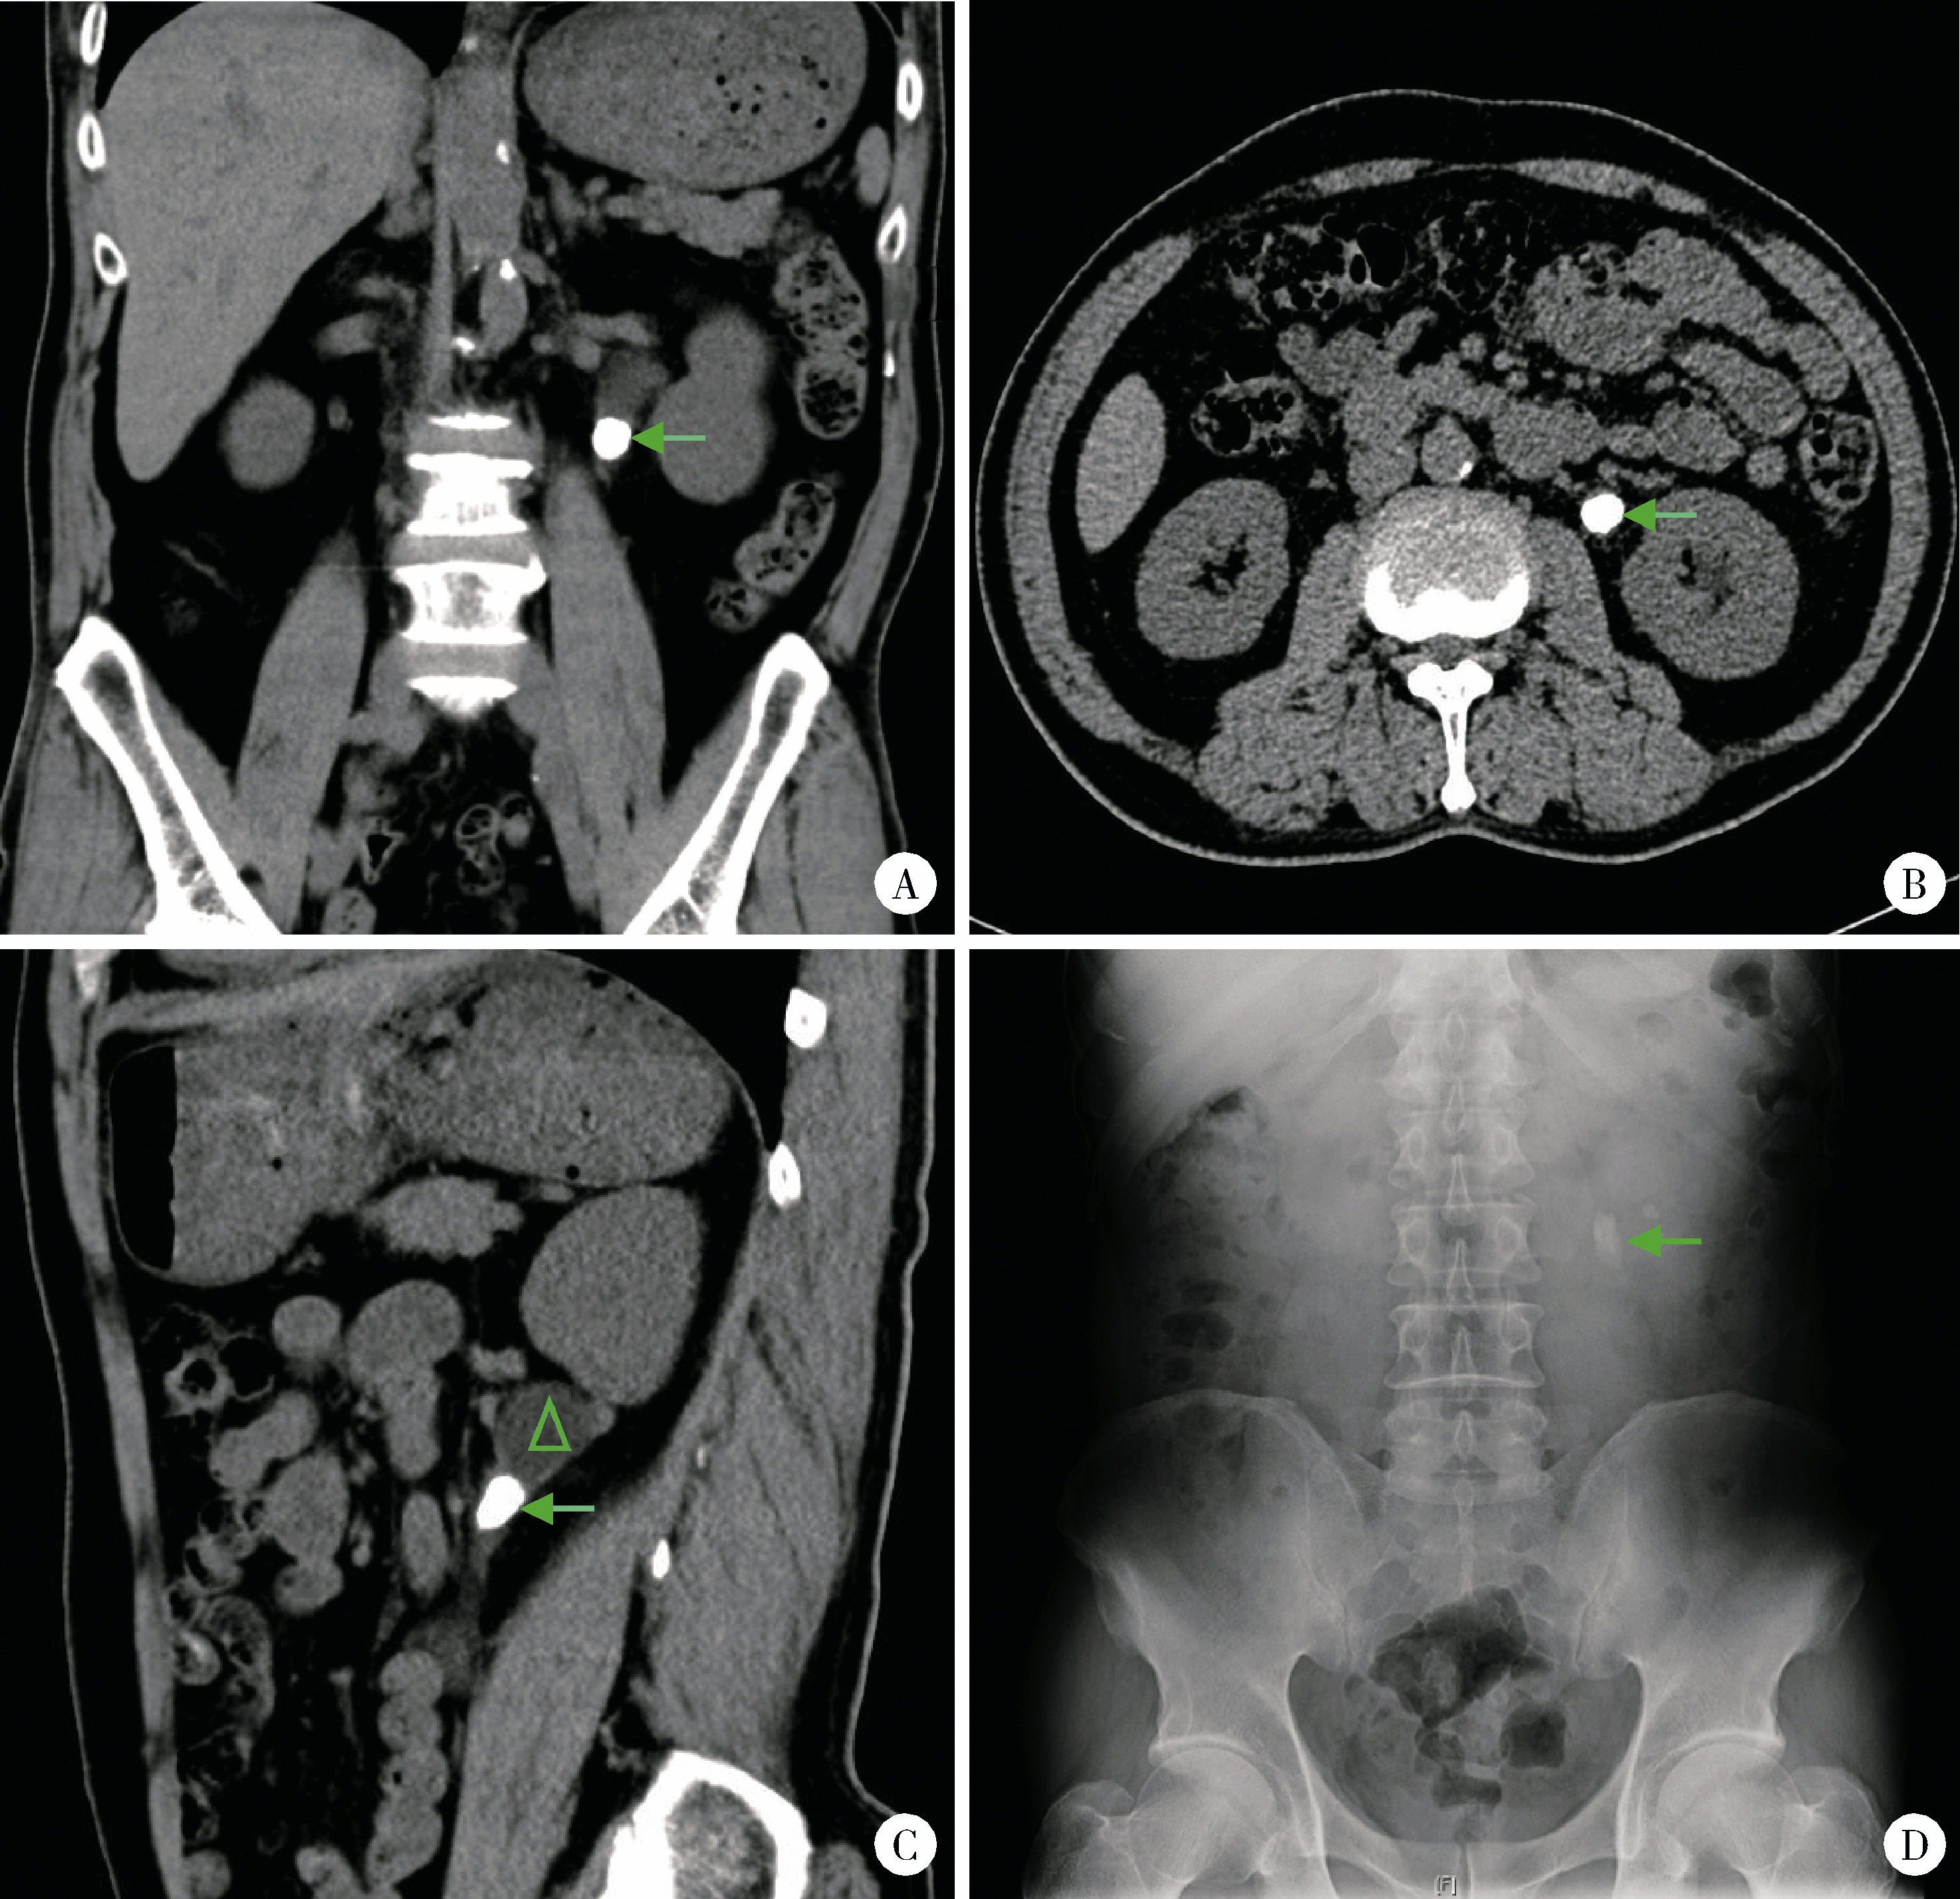

图1 最大径≥1.5 cm输尿管结石的术前影像学表现Figure 1 Imaging characteristics of urolithiasis with largest diameter ≥ 1.5 cm A, coronal CT image, with the arrow indicating the left ureteral calculus, measuring greater than 1.5 cm in length; B, axial CT image, where the arrow marks the location of the calculus; C, sagittal CT image, with the arrow identifying the calculus; notable hydronephrosis due to ureteral obstruction is observed above the calculus (indicated by the triangle); D, the kidneys, ureters, and bladders appearance of a ureteral calculus with a maximum dia-meter of ≥1.5 cm, highlighted by the arrow. |